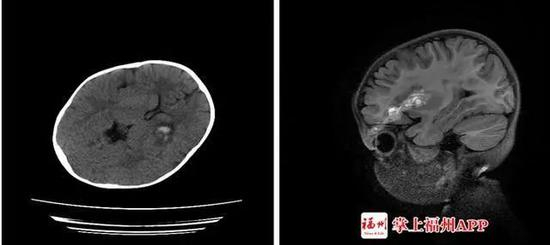

接诊专家介绍,软轴刺入造成了小美开放性颅脑损伤、颅内少量血肿、左眼眶上壁骨折伴左眼眶周围软组织挫裂伤。

家人赶紧把小文送到医院。医生发现,这根塑料杆有筷子般粗,插入了小文的左眼。CT检查显示,异物已进入颅内,导致颅内出血。